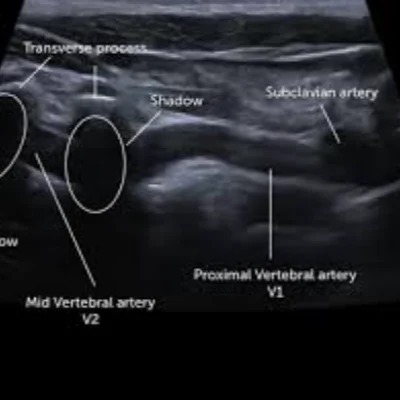

Doppler Ultrasound

Doppler studies assess blood flow in arteries and veins, helping detect

Deep vein thrombosis (DVT)

Peripheral artery disease

Carotid artery narrowing

Placental blood flow in pregnancy

These scans are crucial for vascular health and prenatal monitoring, offering dynamic insights into circulation.